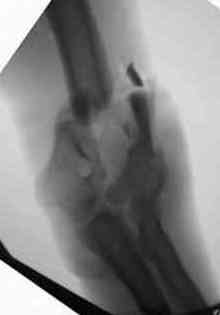

видели, все винты self tapping. Во втором случае у пациента с открытым многооскольчатым

переломом дистального плеча на 4 сутки выполнен остеосинтез. Обратите внимание =доступ без

резекции олекранона,медленная и ювелирная работа нетипичным для нас инструментом

закончена полным восстановлением анатомии локтевого сустава. В небольшой дефект залит

БМП\OP-1 Stryker ,продукт роста клеток человека в генной модификации\. Для профилактики

гетеротопической оссификации ряд врачей применяют облучение на 2-3 сутки.